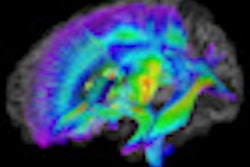

| MR image (left) illustrates anatomic regions of interest for the primary auditory cortex and superior temporal gyrus. Activation maps (middle and right) show greater activity within the superior temporal gyrus but not the auditory cortex in the control group compared with the nonsedated autism group, and greater activation within both the superior temporal gyrus and auditory cortex in the nonsedated subjects compared with the sedated autism group. Image courtesy of Radiology. |

Upon analysis of the functional MR images and measurements, Lai and colleagues found that activity in the primary auditory cortex did not differ between the autistic children and the healthy control subjects. However, they did see a difference in mean amplitude and spread of activity in the superior temporal gyrus between autistic and healthy children (p = 0.001).

Among 10 (83%) of the 12 autistic children who were not sedated, the researchers noted a decrease of at least one standard deviation below the level of the healthy group.